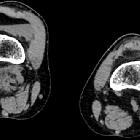

(lipohemarthrosis) • Tibia plateau fracture with lipohemarthrosis (and FBI sign) - Ganzer Fall bei Radiopaedia

The FBI sign is an acronym referring to the components that form a lipohemarthrosis. It stands for:

- fat

- blood

- interface